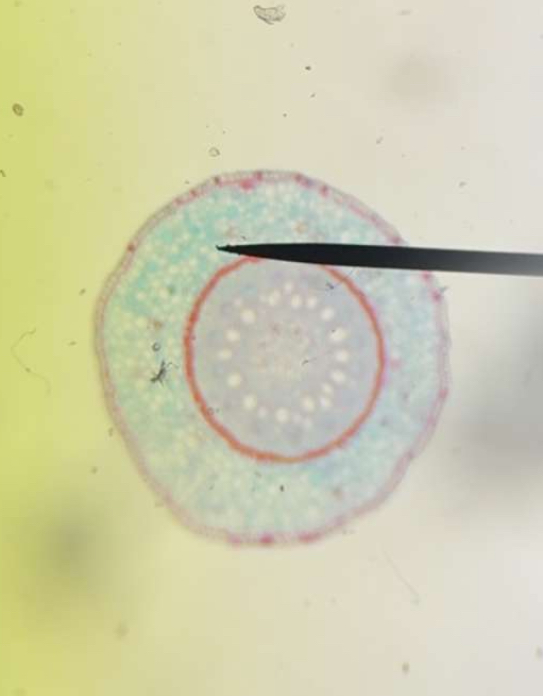

🔬 Students in Mrs. Staines’ science class dove into a hands-on microscope lab! They identified the parts of the microscope, practiced proper use, and explored a variety of prepared slides filled with fascinating specimens. #4theT